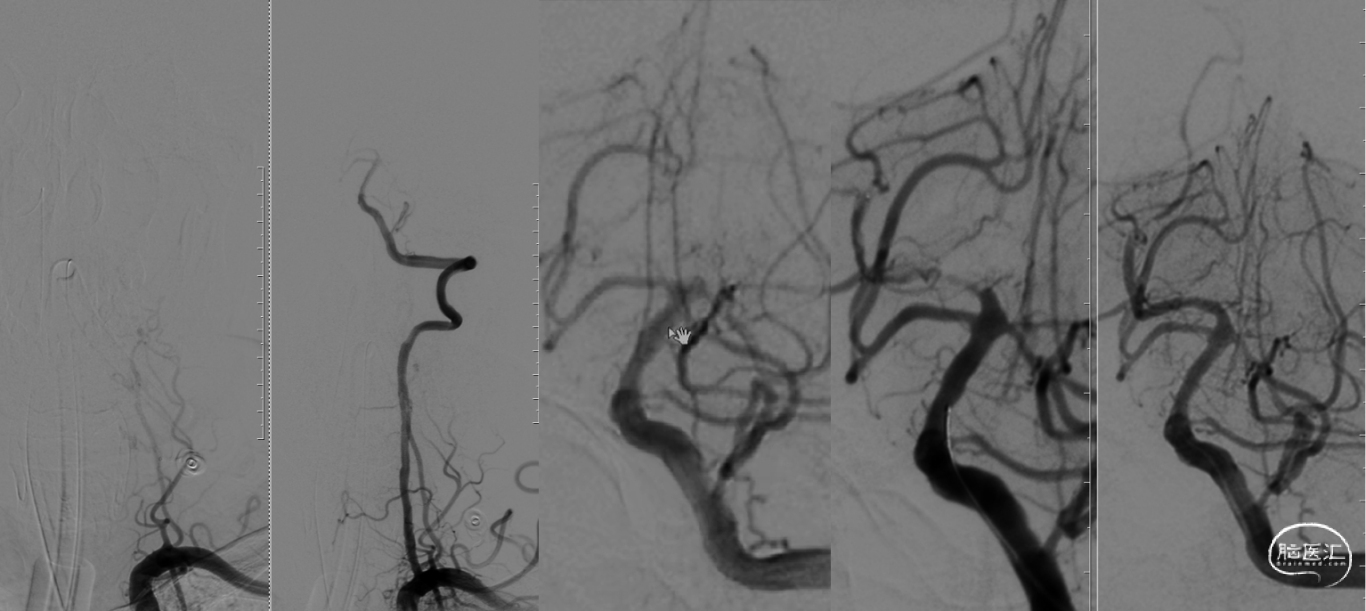

DSA评估:主动脉弓+左侧锁骨下

DSA评估:右椎+双侧颈内动脉

WAIN-CKI-200导丝通过失败;冠脉PTCA导丝顺利通过闭塞段。